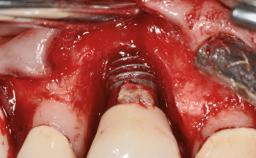

Peripheral Giant-cell Granuloma Associated with Peri-implant Tissues

Giant-cell granulomas (GCG) of the jaws are benign reactive lesions of unknown etiology, unrelated to giant-cell tumors (osteoclastomas), which are defined as benign but locally destructive and aggressive neoplasms (Jundt and coworkers 2005). Depending on their localization at the initial diagnosis, GCG are dived into central (CGCG) and peripheral (PGCG) types. CGCGs occur within the jawbones and appear as unilocular or multilocular radiolucent lesions. The incidence in the general population is very low. They are more commonly found in the mandible, mainly in children and young adults—patients are generally younger than 30 years—and have a greater incidence in females (Heithersay and coworkers 2002). The clinical behavior of CGCGs varies from slowly growing asymptomatic swellings to aggressive lesions that may result in pain, cortical perforation of the affected jaw site, and root resorption (de Lange and coworkers 2007).